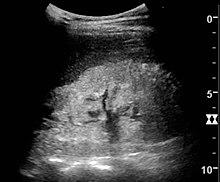

Ultrasound of a kidney with nephrotic syndrome. There is a hyperechoic kidney without demarcation of the cortex and medulla.[27]

Along with obtaining a complete medical history, a series of biochemical tests are required in order to arrive at an accurate diagnosis that verifies the presence of the illness. In addition, imaging of the kidneys (for structure and presence of two kidneys) is sometimes carried out, and/or a biopsy of the kidneys. The first test will be a urinalysis to test for high levels of proteins,[28] as a healthy subject excretes an insignificant amount of protein in their urine. The test will involve a 24-hour bedside urinary total protein estimation. The urine sample is tested for proteinuria (>3.5 g per 1.73 m2 per 24 hours). It is also examined for urinary casts, which are more a feature of active nephritis. Next a blood screen, comprehensive metabolic panel (CMP) will look for hypoalbuminemia: albumin levels of ≤2.5 g/dL (normal=3.5-5 g/dL). Then a Creatinine Clearance CCr test will evaluate kidney function particularly the glomerular filtration capacity.[29] Creatinine formation is a result of the breakdown of muscular tissue, it is transported in the blood and eliminated in urine. Measuring the concentration of organic compounds in both liquids evaluates the capacity of the glomeruli to filter blood. Electrolytes and urea levels may also be analysed at the same time as creatinine (EUC test) in order to evaluate kidney function. A lipid profile will also be carried out as high levels of cholesterol (hypercholesterolemia), specifically elevated LDL, usually with concomitantly elevated VLDL, is indicative of nephrotic syndrome.